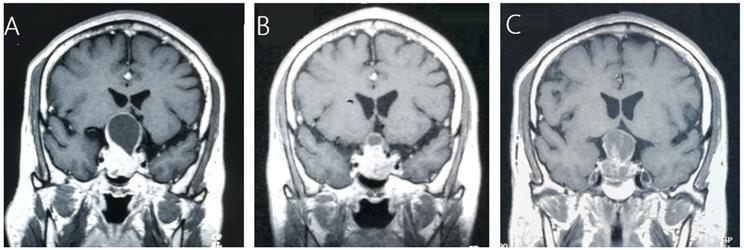

Tumor control

Tumor control was confirmed by follow-up MR imaging in 128 patients (86.5%). The data was shown in Table 2. Tumor shrank in 111 patients (75%) and remained stable in 17 patients (11.5%). Tumor progression was confirmed in 20 patients (13.5%) (Figure 1). The median time of tumor progression was 35.1 months (Range: 10.7 - 99.2 months) after GKRS. Of the 16 patients with progression due to tumor regrowth, 9 patients underwent repeat GKRS, 2 patients underwent surgery, 2 patients underwent close observation, and 3 patients were lost to follow-up. Of the 4 patients with progressive cystic enlargement, 2 patients underwent surgery, 2 patients underwent close observation. The progression-free survival rates were 99%, 91%, 88% and 74% at 1, 3, 5 and 10 years after postsurgical GKRS respectively (Figure 2).

Figure 1

A 45-year-old male patient with residual NFPA received GKRS (10.5Gy/30%) at 4.9 months after surgery and tumor progression due to progressive cystic enlargement was detected at 32.5 months after GKRS. A, MRI showed pituitary giant adenoma in sellar area. B, MRI showed residual tumor at 4.9 months after surgery. C, MRI showed tumor enlargement due to progressive cystic enlargement at 32.5 months after GKRS.